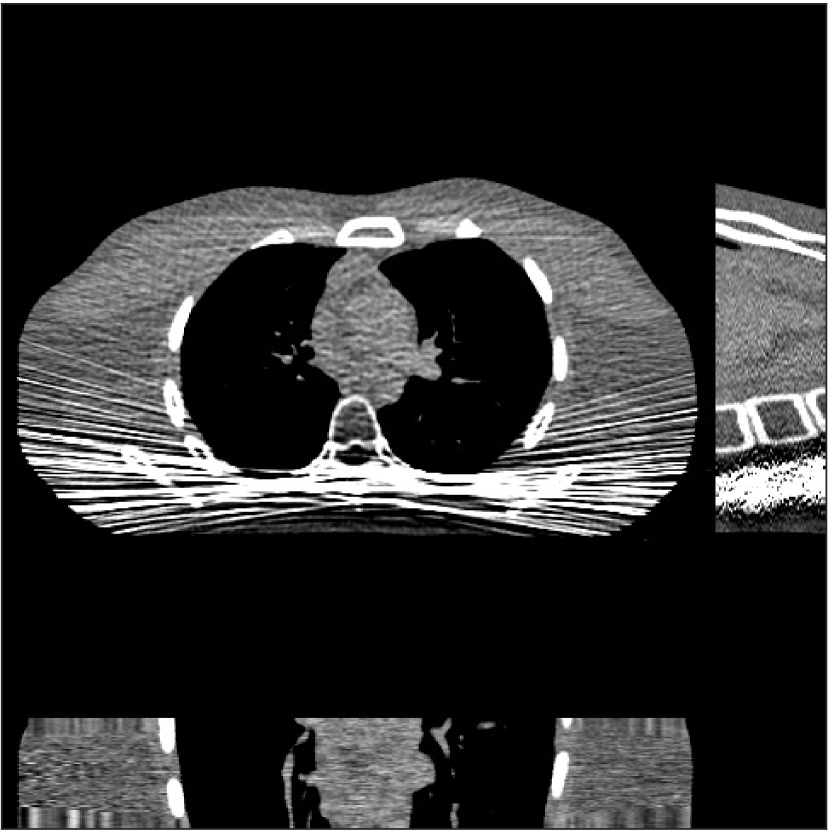

Refer to caption

Figure 1: Reconstruction targeted ROI of the true XCAT phantom displayed with central slices along the axial, sagittal and coronal directions. The display window is [800, 1200] HU.

We simulated 3D axial cone-beam scans using a 840×840×9684084096840\times 840\times 96 XCAT phantom with Δx=Δy=0.4883subscriptΔ𝑥subscriptΔ𝑦0.4883\Delta_{x}=\Delta_{y}=0.4883 mm and Δz=0.625subscriptΔ𝑧0.625\Delta_{z}=0.625 mm. We generated sinograms of size 888×64×98488864984888\times 64\times 984 using GE LightSpeed cone-beam geometry corresponding to a mono-energetic source with I0=1×104subscript𝐼01superscript104I_{0}={\color[rgb]{0,0,0}1\times}10^{4}, 5×1035superscript1035\times 10^{3}, 3×1033superscript1033\times 10^{3}, and 2×1032superscript103{2\times 10^{3}} incident photons per ray and no scatter, respectively. Tab. I shows percentages of non-positive measurements under different dose levels. We set these non-positive measurements to 1×1051superscript1051\times 10^{-5} for generating the post-log sinogram that PWLS-based methods rely on [13]. We reconstructed the 3D volume with a size of 420×420×9642042096420\times 420\times 96 at a coarser resolution of Δx=Δy=0.9766subscriptΔ𝑥subscriptΔ𝑦0.9766\Delta_{x}=\Delta_{y}=0.9766 mm and Δz=0.625subscriptΔ𝑧0.625\Delta_{z}=0.625 mm. The patch size during reconstruction was 8×8×88888\times 8\times 8 and the stride was 3×3×33333\times 3\times 3. For evaluating reconstruction performance, we chose an ROI that was composed of the central 64 out of 96 axial slices, and refer to it as the reconstruction targeted ROI. Fig. 1 shows the central slices of the true XCAT phantom inside this ROI along three directions. In the reconstruction stage of PWLS-ULTRA and SPULTRA, we used 4 iterations for the image update step, i.e., P=4𝑃4P=4, for a good trade-off between algorithms’ convergence and computational costs. We used 121212 ordered subsets, i.e., M=12𝑀12M=12, to speed up the algorithm. The initial image for the ULTRA methods was reconstructed by PWLS-EP, whose regularization parameter was set empirically to ensure good reconstruction quality as βep=213subscript𝛽𝑒𝑝superscript213\beta_{ep}=2^{13} for all the experimented dose cases. We used an analytical filtered back-projection (FBP) method FDK [59] to initialize PWLS-EP. The FDK images of XCAT phantom for all the dose levels are shown in the supplement. Due to the fact that SPULTRA has a similar cost function as PWLS-ULTRA in each outer iteration, we used the same parameter settings for both methods: β=4×104𝛽4superscript104\beta=4\times 10^{4} and γc=4×104subscript𝛾𝑐4superscript104\gamma_{c}=4\times 10^{-4}, which we observed worked well for all the dose levels we tested.